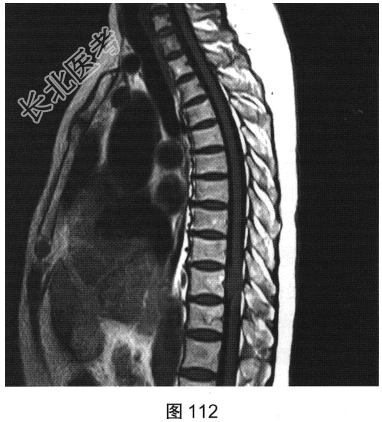

- [材料题] 患者女性,59岁,无明显诱因出现腰背部疼痛伴双下肢麻木1年,久行、久坐、久站或咳嗽、排便时疼痛加重,休息后症状缓解,1个月前腰背部麻木疼痛突发加重,行走100米既感疼痛难忍,伴双下肢无力疼痛。查体:脊柱无明显侧弯,相当于T₁₀平面以下感觉减退,腰椎活动度受限,无紧张,棘突旁压痛、叩痛,向双下肢放射。挺腹试验阳性,跟臀试验(+),双侧直腿抬高试验(一),双下肢小腿外侧、足背感觉稍差,双侧

背伸肌肌力4级;肌张力正常,双侧巴宾斯基征可疑阳性。实验室检查:人类白细胞抗原B27阴性(一),RF<10U/ml(正常值0~15U/ml)。

- 简答题2、患者行MRI检查,如图111~图114所示。根据患者病史及影像学检查,请问其最可能的诊断是什么?

- 简答题3、请对脊膜瘤进行描述。